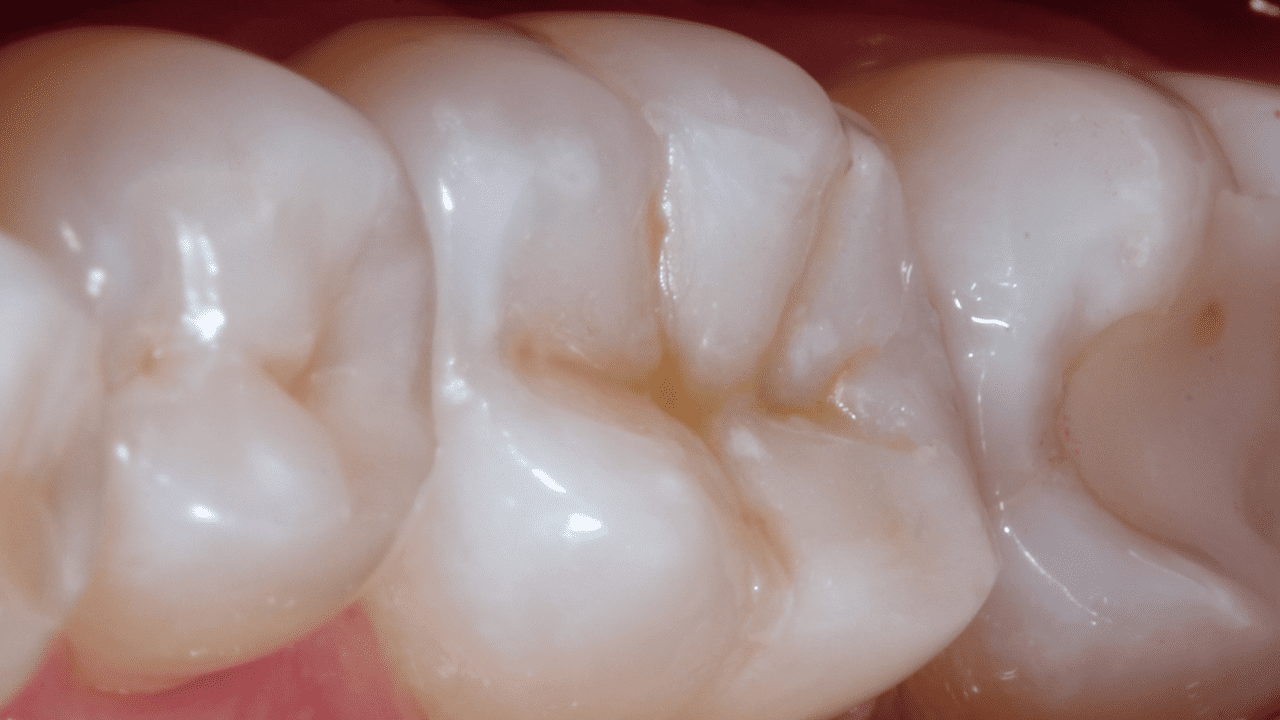

Results: 3-month recall. Occlusal-palatal view depicting excellent gloss retention. Note the characterization and natural appearance obtained with Neo Spectra® ST universal composite A2 and BW.